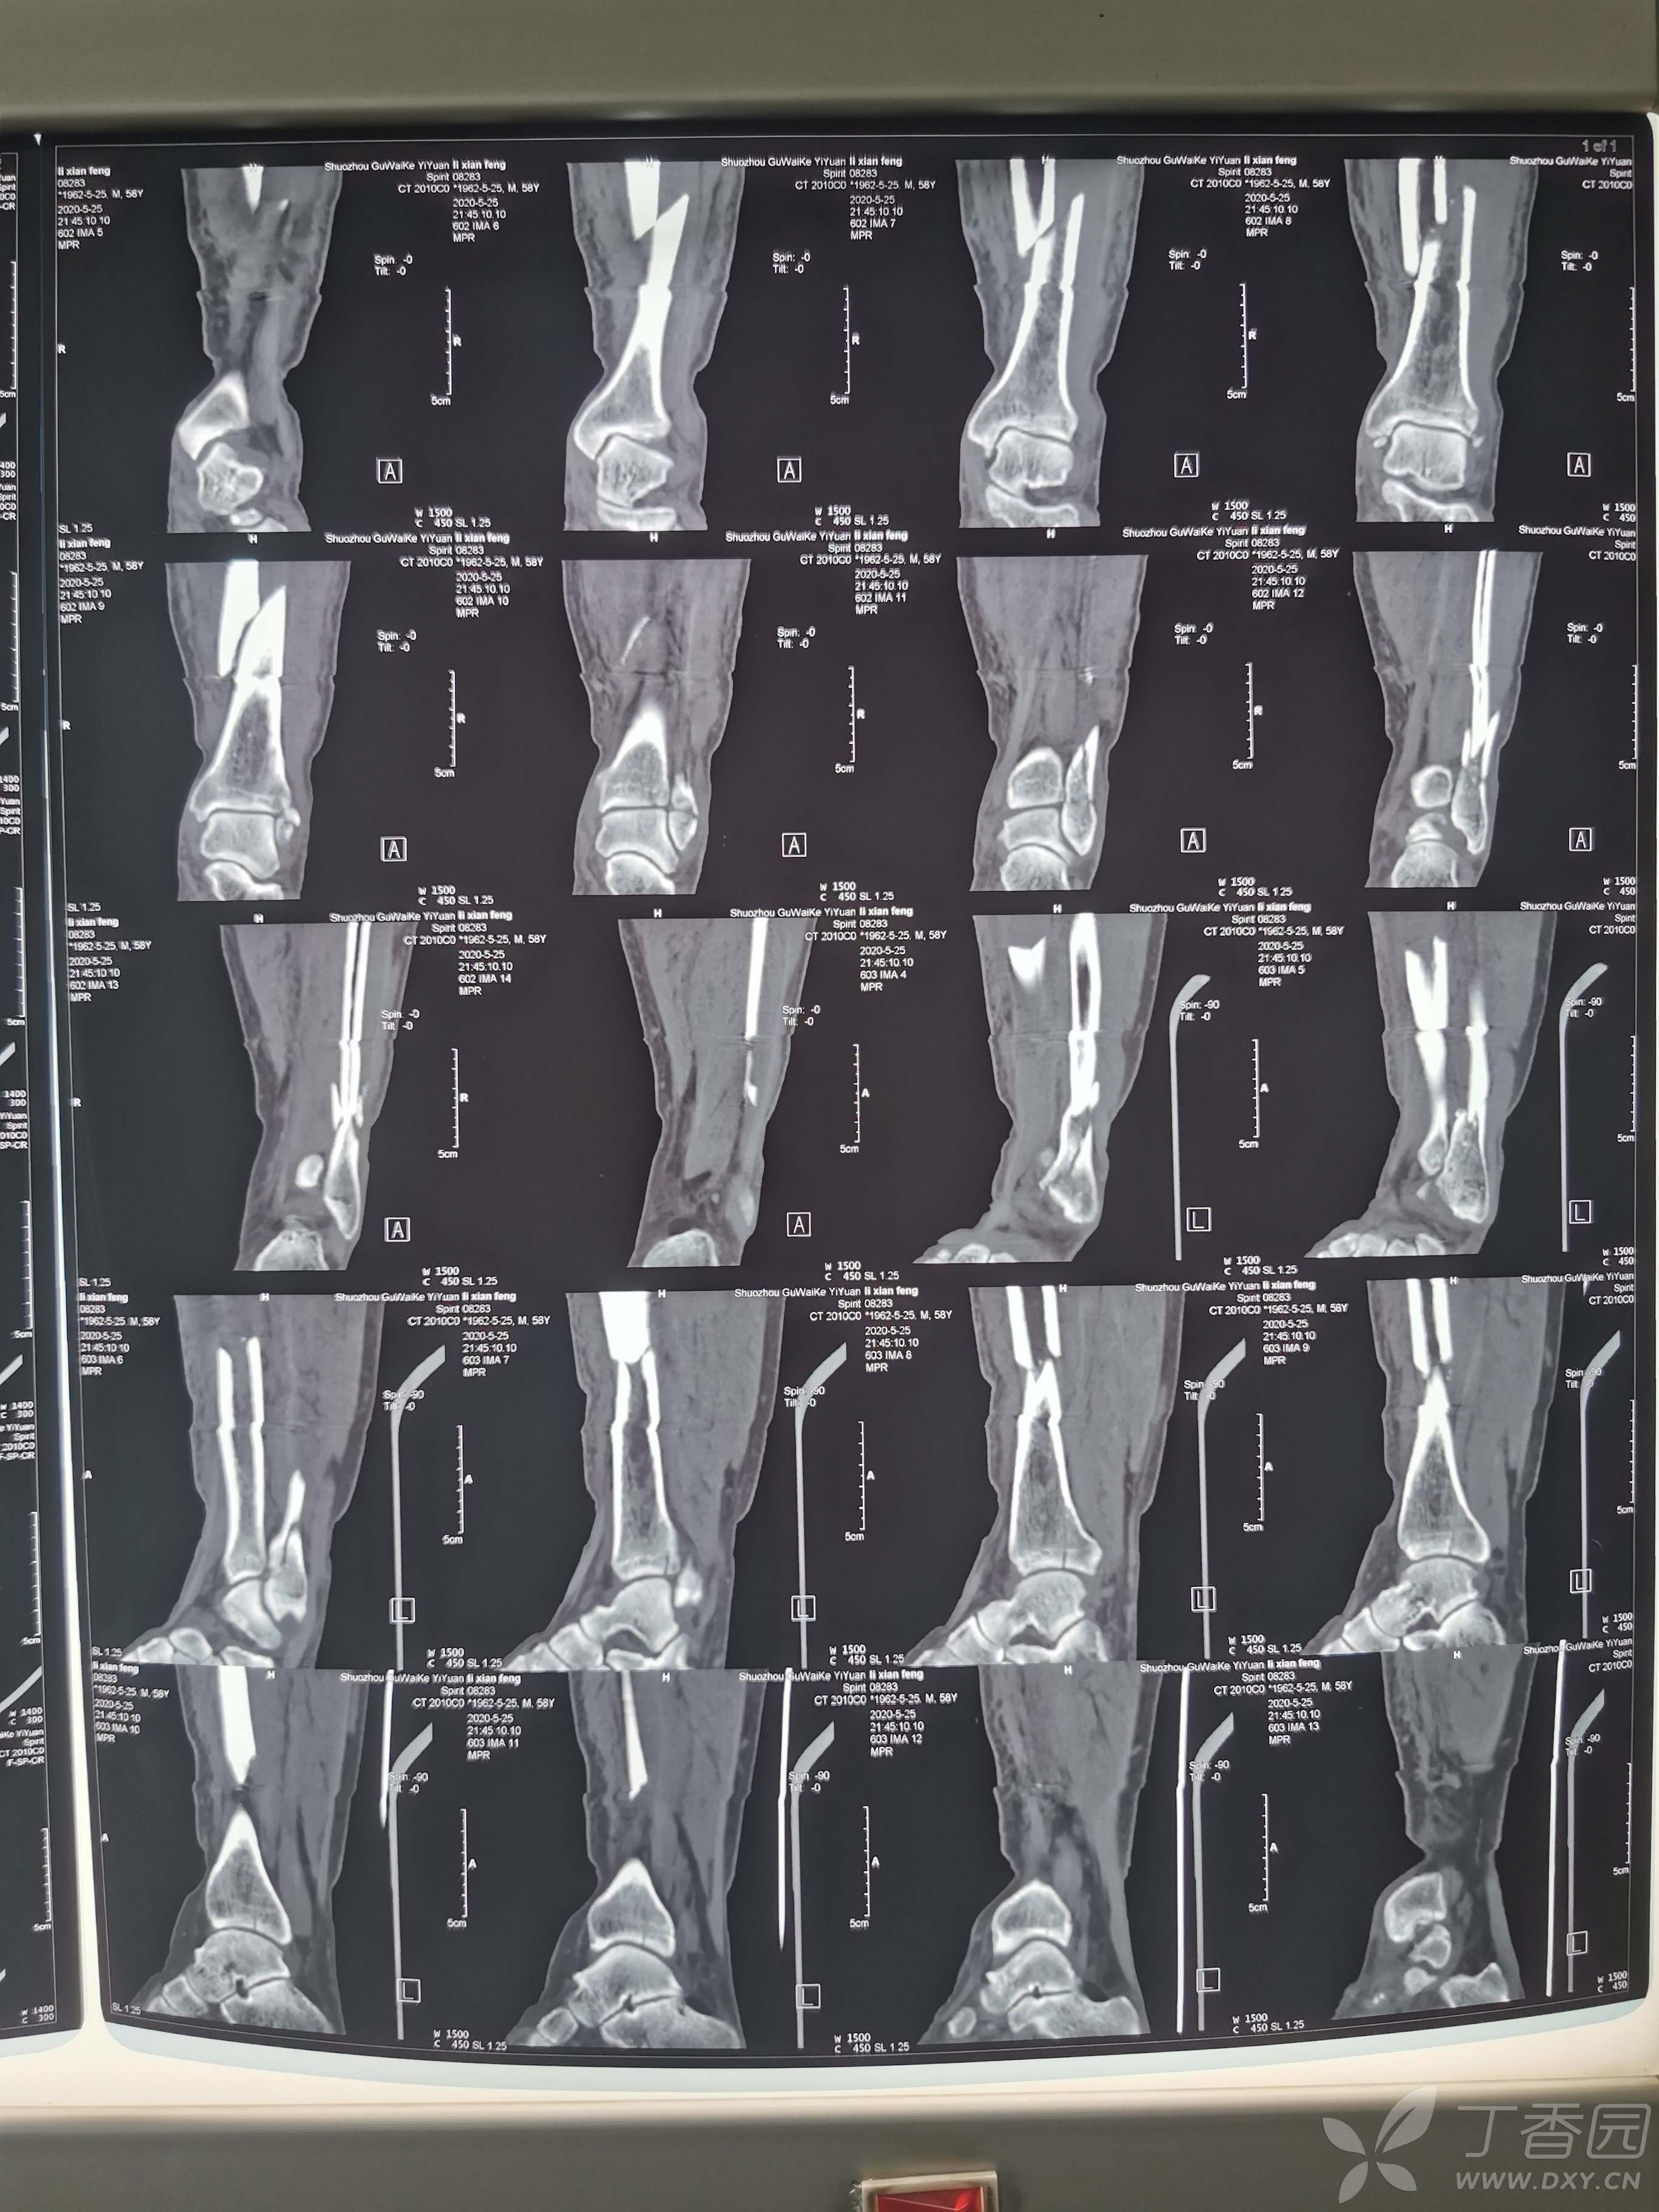

胫腓骨骨折闭合复位带锁钉固定,腓骨钢板固定

患者,男性,54岁,滑倒致伤入院急诊固定